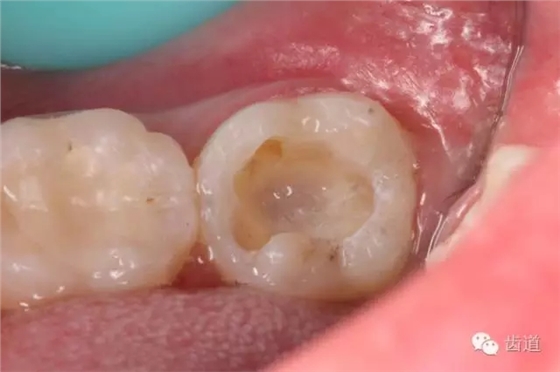

3. 制備嵌體洞型,去盡無(wú)基釉

4. 精細(xì)修整洞型